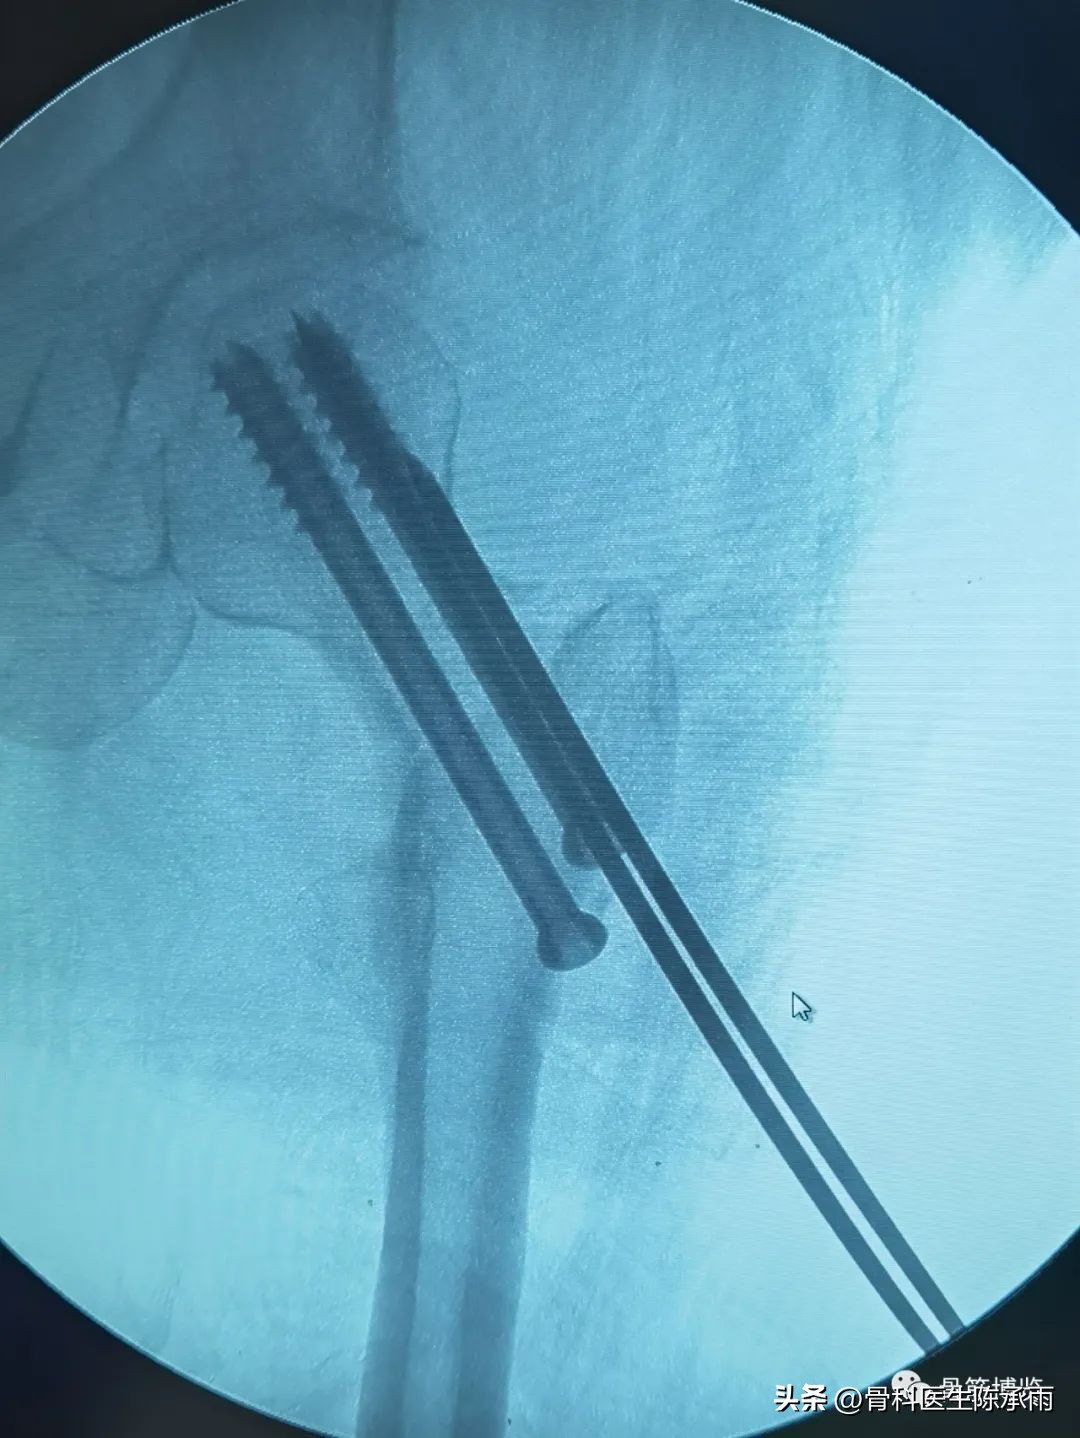

术前尝试闭合复位,效果满意,决定行经皮穿钉,但股骨颈角度不正常,颈部细小,很难容得下3枚直径7.3空心钉,最后1枚空心钉部分切出股骨颈上缘。